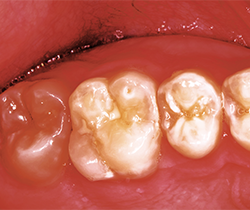

Fig. 3 Fig. 4